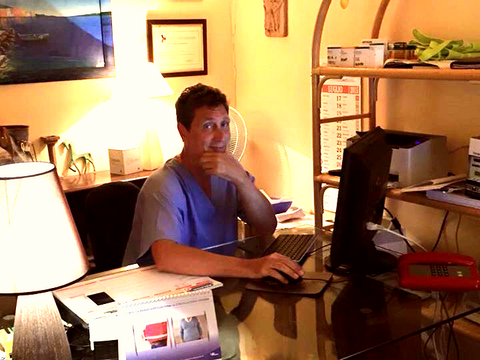

Dott. Angelo Manciocchi

specialista in Chirurgia Vascolare

già Libero Docente Malattie Cardiovascolari

Università Sapienza-Roma